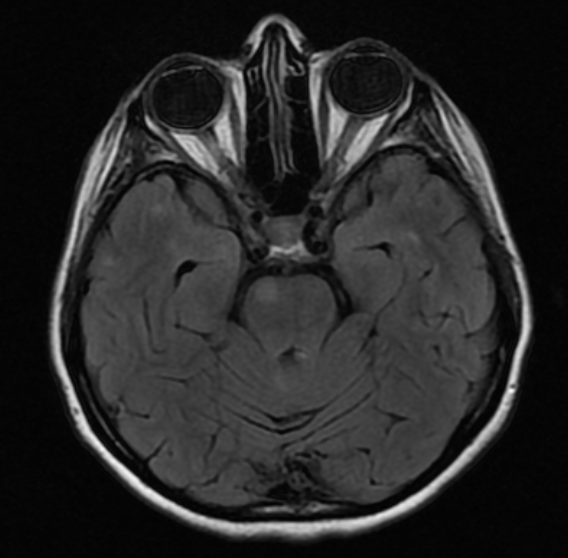

Objetivo: Relatar o caso de recidiva de herpes-zoster (HZ) em paciente com esclerose múltipla (EM) em uso de tratamento imunomodulador (natalizumabe) com evolução favorável. Descrição de caso: Mulher de 39 anos com diagnóstico de EM há 1 ano e 6 meses, previamente tratada com interferon 1a, começou tratamento com natalizumabe, desenvolvendo HZ após três meses de tratamento. HZ foi tratado com aciclovir, por sete dias, via oral. Seguimento ambulatorial após três meses de tratamento mostrou resolução completa das lesões, sem desencadeamento de neuralgia pós-herpética. Conclusões: As novas terapias para a EM podem estar relacionadas a diferentes tipos de efeitos adversos. Nem todos os casos de HZ, associados com novas terapias para EM, evoluem de forma desfavorável. Estudos são necessários para reconhecer os fatores de riscos para as formas graves de HZ em tais pacientes.